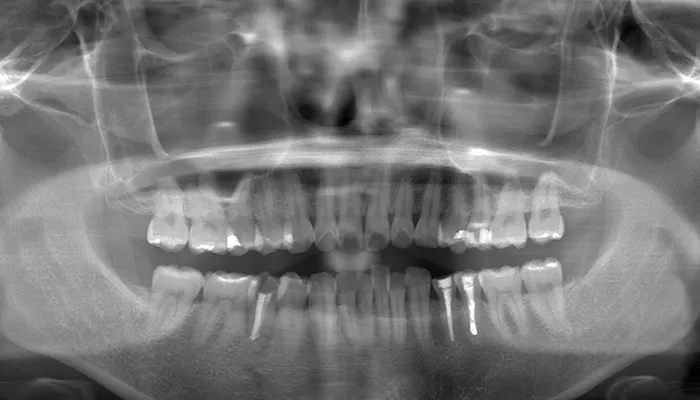

Before

初診時の口腔内写真

術前の口腔内写真

右下5番は大きく崩壊しており、保存不可能な状態でした。

また、下顎前歯部を中心に叢生があり、歯列が不均一でした。咬合関係が不安定で、清掃性も低下していました。

全体的に歯の色もやや黄みを帯びており、患者様からも審美的な改善希望が強くありました。